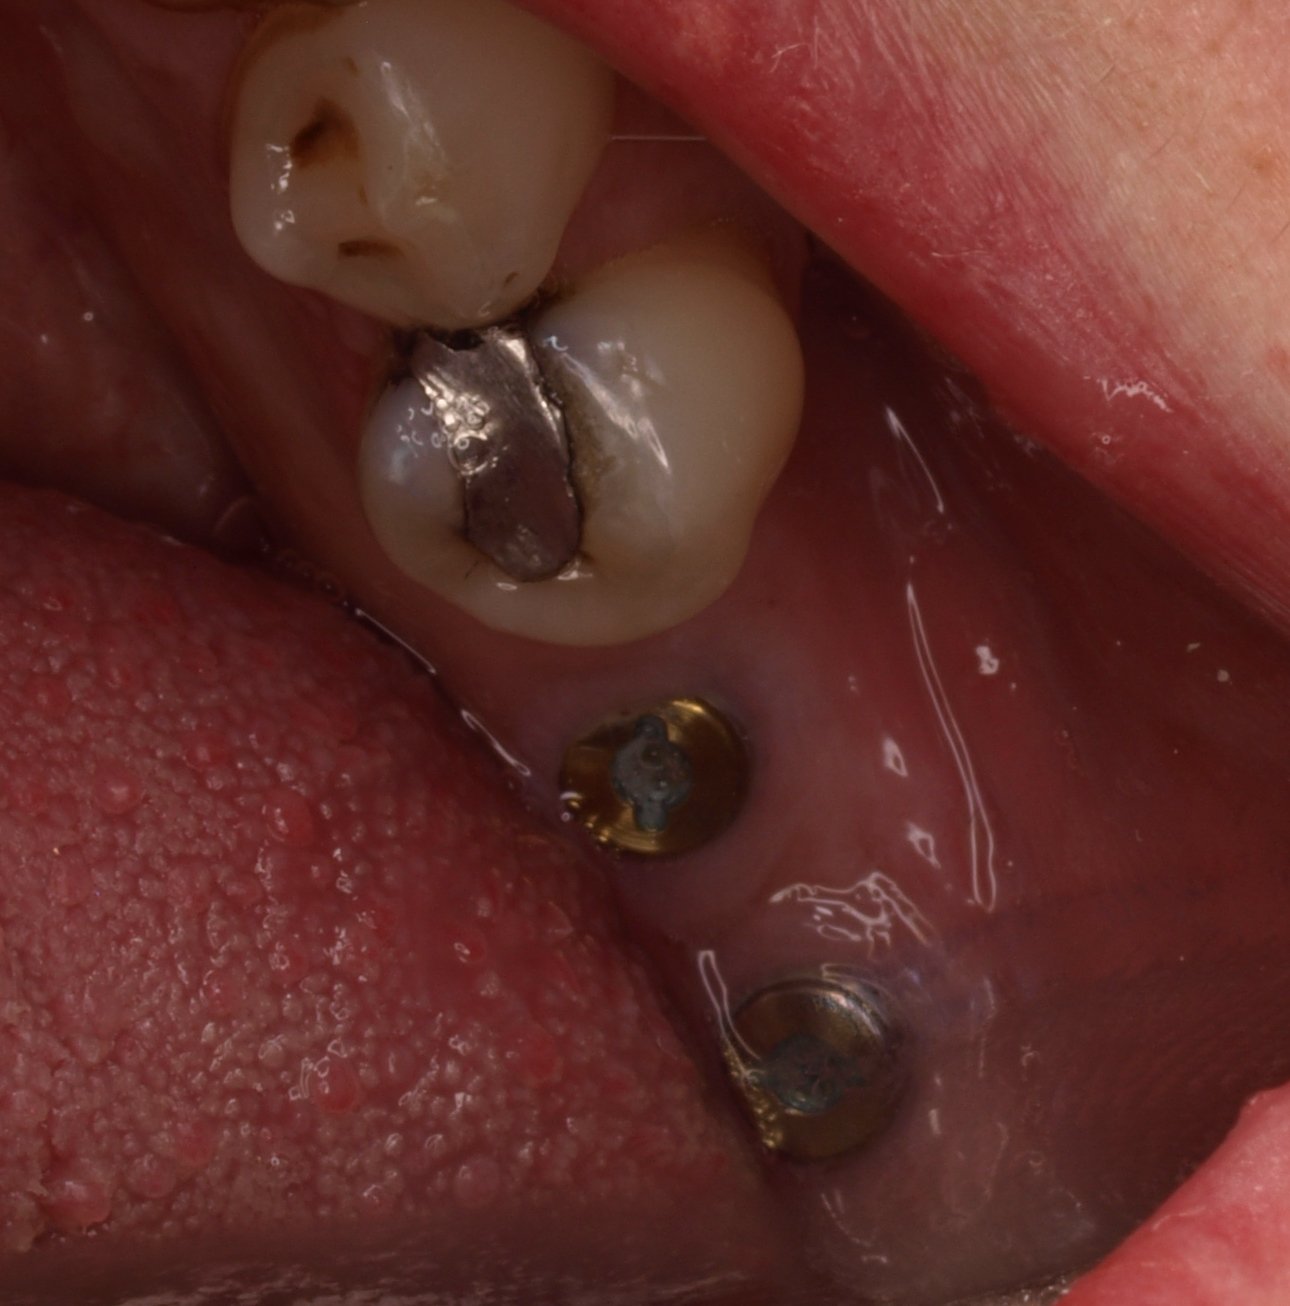

No se que implantes son. Piezas 34,35,44 y45

Buenas tardes. Paciente acude a consulta con implantes colocados en otra clínica en 34,35, 44 y 45. No le llegaron a colocar las coronas. Traspasaron la clínica y al ir [...]